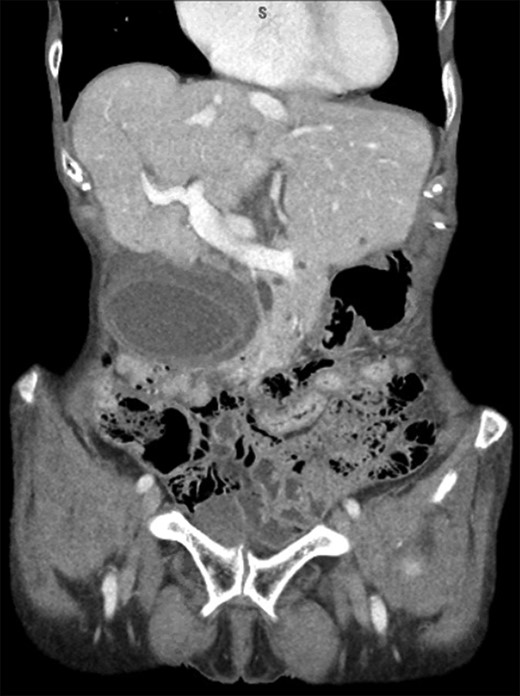

A 77-year-old female presented with acute right upper quadrant (RUQ) pain with associated nausea for 12 hours. Pain was described as dull and more severe after eating. The patient had prior episodes of this pain, occurring for the last several years. She admitted weight loss and denied any fevers, chills or vomiting. Medical history included hypothyroidism, hyperlipidemia, malabsorption problem for which she takes B12 and folic acid supplements. Surgical history included appendectomy. She denied any tobacco or alcohol use. Abdominal exam demonstrated a soft, non-distended abdomen with a palpable mass in the RUQ, RUQ tenderness to palpation without rebound or guarding. Lab values were significant for an elevated leukocytosis; chemistry and hepatic function panel within normal limits. CT scan demonstrated a distended hydropic appearing gallbladder with pericholecystic fluid and wall edema without evidence of gallstones (Fig. 1) and a common bile duct of 9 mm. Subsequent RUQ ultrasound revealed a dilated gallbladder with a thickened wall and a small amount of pericholecystic fluid, suggestive of acalculus cholecystitis. The patient was admitted, started on Cefepime and Flagyl, and scheduled for a laparoscopic cholecystectomy. Upon entering the abdomen, a large necrotic, gangrenous appearing gallbladder was noted (Fig. 2a–d). It had maneuvered itself over the top of the liver and completely necrosed its base. The gallbladder was extremely distended, encompassing much of the patient’s RUQ. The common bile duct was able to be identified. The gallbladder was not detorsed due to risk of toxin release into circulation as the gallbladder was gangrenous. Decompression of the gallbladder was not attempted due to concern for a possible malignancy. A 12 mm trocar was placed in the RLQ and a GIA stapler with Peristrips was used to completely transect the base of the gallbladder, including the cystic artery and duct. The gallbladder was placed in a large EndoCatch bag and the umbilical incision was extended to remove it from the abdomen. Hemostasis was achieved at the staple line and no other evidence of abnormalities were noted. The patient tolerated the procedure well. The patient had an uncomplicated postoperative course. Her postoperative hepatic function panel remained within normal limits. Histopathology was consistent with acute cholecystitis with gallbladder hemorrhage and necrosis (Fig. 3).

CT scan demonstrating a distended hydropic appearing gallbladder with pericholecystic fluid and wall thickening.